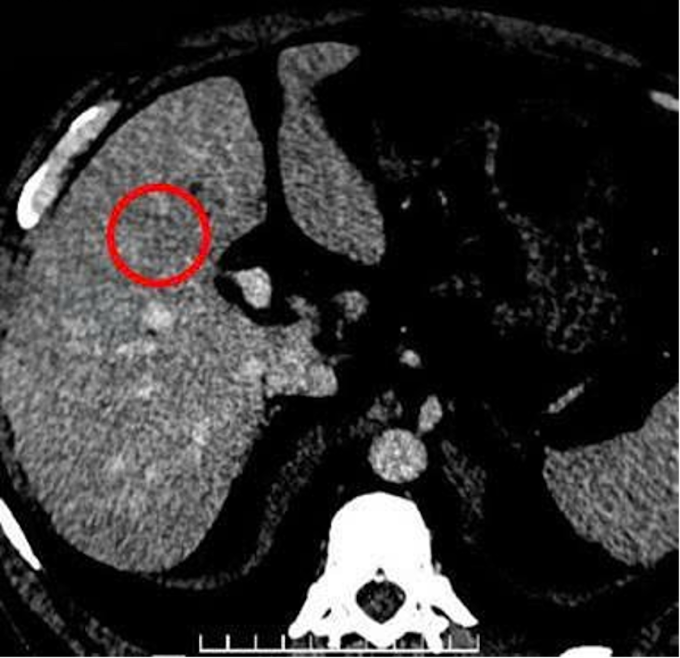

Gần đây, ông thường xuyên mệt mỏi, ăn uống kém, đau âm ỉ vùng hạ sườn phải, đến Bệnh viện Đa khoa Tâm Anh TP HCM khám. Chụp cắt lớp vi tính (CT) cho thấy tại phân thùy 4 của gan có một khối tổn thương giảm đậm độ, kích thước khoảng 22×24 mm, tăng quang rõ ở thì động mạch. Tại các hạ phân thùy 6 và 7 còn ghi nhận thêm một vài nốt nhỏ kích thước khoảng 5 mm. Sinh thiết gan dưới hướng dẫn siêu âm cho kết quả ung thư biểu mô tế bào gan (hepatocellular carcinoma – HCC) ở giai đoạn sớm.

Kết quả CT cho thấy tổn thương gan (khoanh tròn màu đỏ). Ảnh: Bệnh viện Đa khoa Tâm Anh